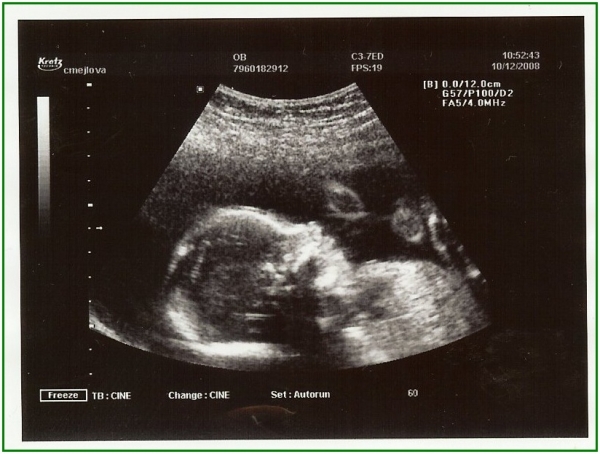

Pod pokličkou potřetí